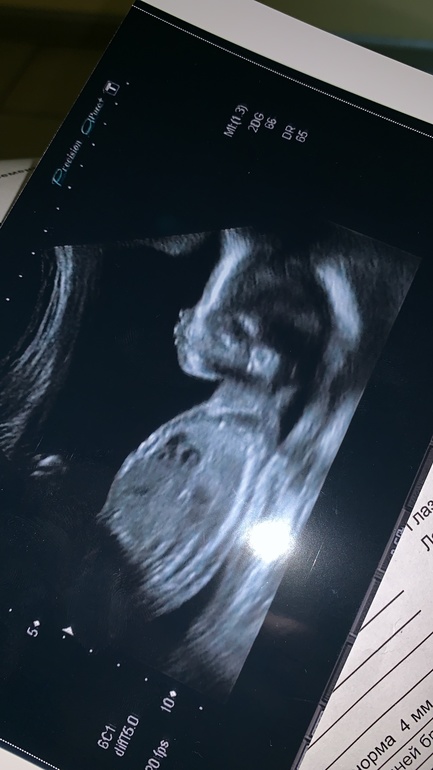

Вопросы про УЗИ, обследования и анализы: что, где, как, когда?Ну,отчитаюсь,сходили мы сегодня на второй. Папа наш чуть телек не целовал на стене)) рассмотрели деваху-зевала пока светили. Коляску кст,вчера купили,но до сих пор не верю во все происходящее-пока в коляске спят коты )))) сделали фото-мама сказала-похожа на меня)) я пока никого не вижу)) нос прямой и курносый мой,конечно, а так.... но точно будет волосатая)))

мы меня для этой фото 20 минут вертели, и спать укладывали-не хотела фотографироваться-все в анфас проворачивалась)))